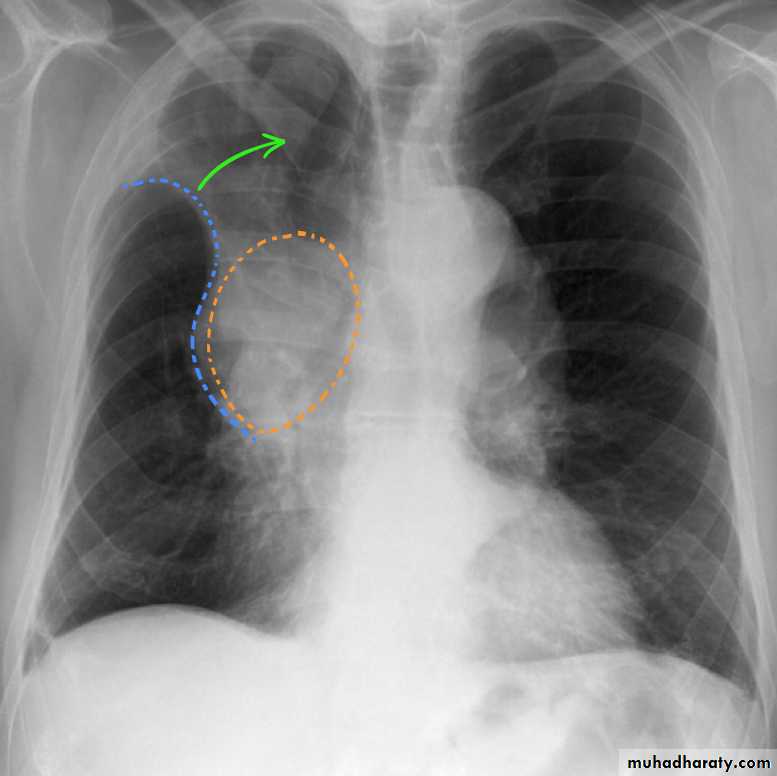

Plain filmExcept in the case of very advanced disease with bulla formation, chest radiography does not image emphysema directly, but rather infers the diagnosis due to associated features :

hyperinflation:

1.flattened hemidiaphragm(s): most reliable sign

2.ncreased and usually irregular radiolucency of the lungs

9.vascular changes paucity of blood vessels ( absent pulmonary markings in outer 1/3 of the lung fields )

10 .pulmonary arterial hypertension

increased calibre of central arteries

right ventricular enlargement